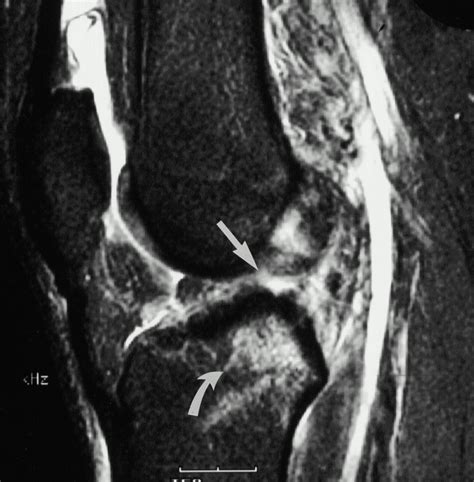

• Imaging Tests: X-rays, MRI, or CT scans may be used to visualize the bone and surrounding tissues. MRI is particularly useful for detecting bone contusions.

A bone contusion knee can occur in conjunction with other knee injuries, such as ligament tears or meniscal injuries. It is important to address all aspects of the injury for effective management. Common co-occurring injuries include:

• Ligament Tears: Injuries to the ligaments that stabilize the knee, such as the anterior cruciate ligament (ACL) or medial collateral ligament (MCL).

• Meniscal Injuries: Tears or damage to the menisci, which act as shock absorbers in the knee joint.